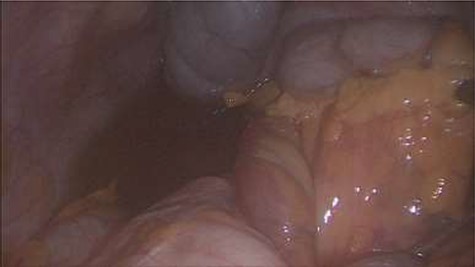

Emergency diagnostic laparoscopy was performed and findings were: 180 degree volvulus of terminal ileum, cecum and ascending colon overlapped each other and overriding the right loop of the liver, the lateral attachment of the right colon was long dilated and floppy (Figs 5 and 6). The dudeno-jejenal flexure was malrotated and lying in left upper quadrant just below to splenic flexure. Three congenital bands were found tilted around the terminal ileum, cecum and base of the appendix. Turbid free fluids with no evidence of infection also noted in the right upper quadrant and right para-colic gutter (Fig. 7). Otherwise, bowels were found healthy and viable. A healthy retrocecal and subserosal appendix was also noted intraoperatively. We converted to open Laparotomy and proceeded with right hemicolectomy due to complex intraoperative findings. The postoperative period was uneventful, and patient was discharged at home on postoperative Day 7.

Showing 180 degree volvulus of terminal ileum, cecum and ascending colon overlapped each other and overriding the right loop of the liver.

Showing floppy dilated cecum ileum and ascending colon twisted around the liver and mesentery.